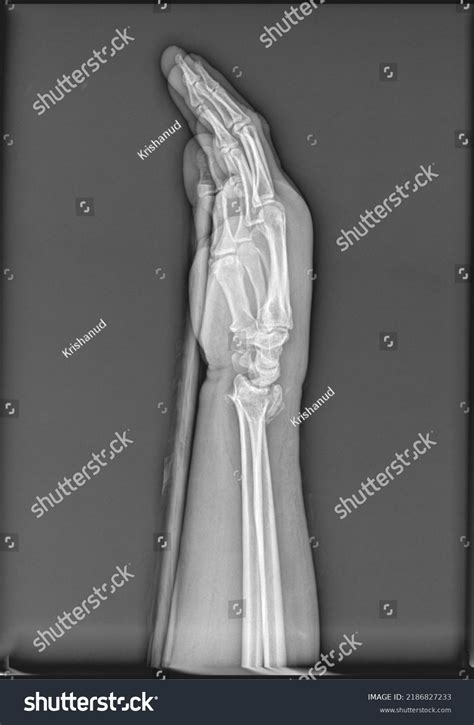

A forearm X-ray is one of the most common diagnostic imaging procedures performed in emergency departments, urgent care centers, and orthopedic clinics. Whether you have suffered a sudden fall, a sports-related injury, or are experiencing unexplained chronic pain, this imaging tool provides doctors with a vital, non-invasive look beneath the skin. By utilizing small amounts of electromagnetic radiation to create images of the bones in the forearm—specifically the radius and the ulna—medical professionals can accurately diagnose fractures, dislocations, and various other structural abnormalities. Understanding the procedure, why it is requested, and what the results mean can help demystify the process and prepare you for your visit to the radiology department.

Understanding the Anatomy of the Forearm

To interpret a forearm X-ray, it helps to understand the anatomy involved. The forearm consists of two long bones that work together to allow for flexibility and rotation:

The Radius: Located on the side of the thumb, the radius is the bone that primarily allows the forearm to rotate, enabling you to turn your palm up or down.

The Ulna: Located on the side of the pinky finger, the ulna is larger at the elbow and helps form the hinge joint necessary for bending the arm.

Injuries to these bones often occur during a "FOOSH"—an acronym for Fall On an Outstretched Hand. When you fall, the impact travels up through the wrist and can easily fracture either or both of these bones. Because they are anatomically linked, a fracture in one often causes structural stress or a corresponding dislocation in the other.